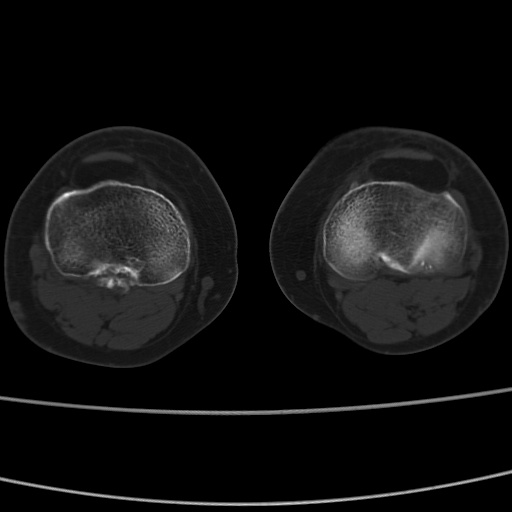

女性,50岁。【请提供患者临床症状体征】

右膝关节退行性改变,关节游离鼠。

右膝关节退行性改变